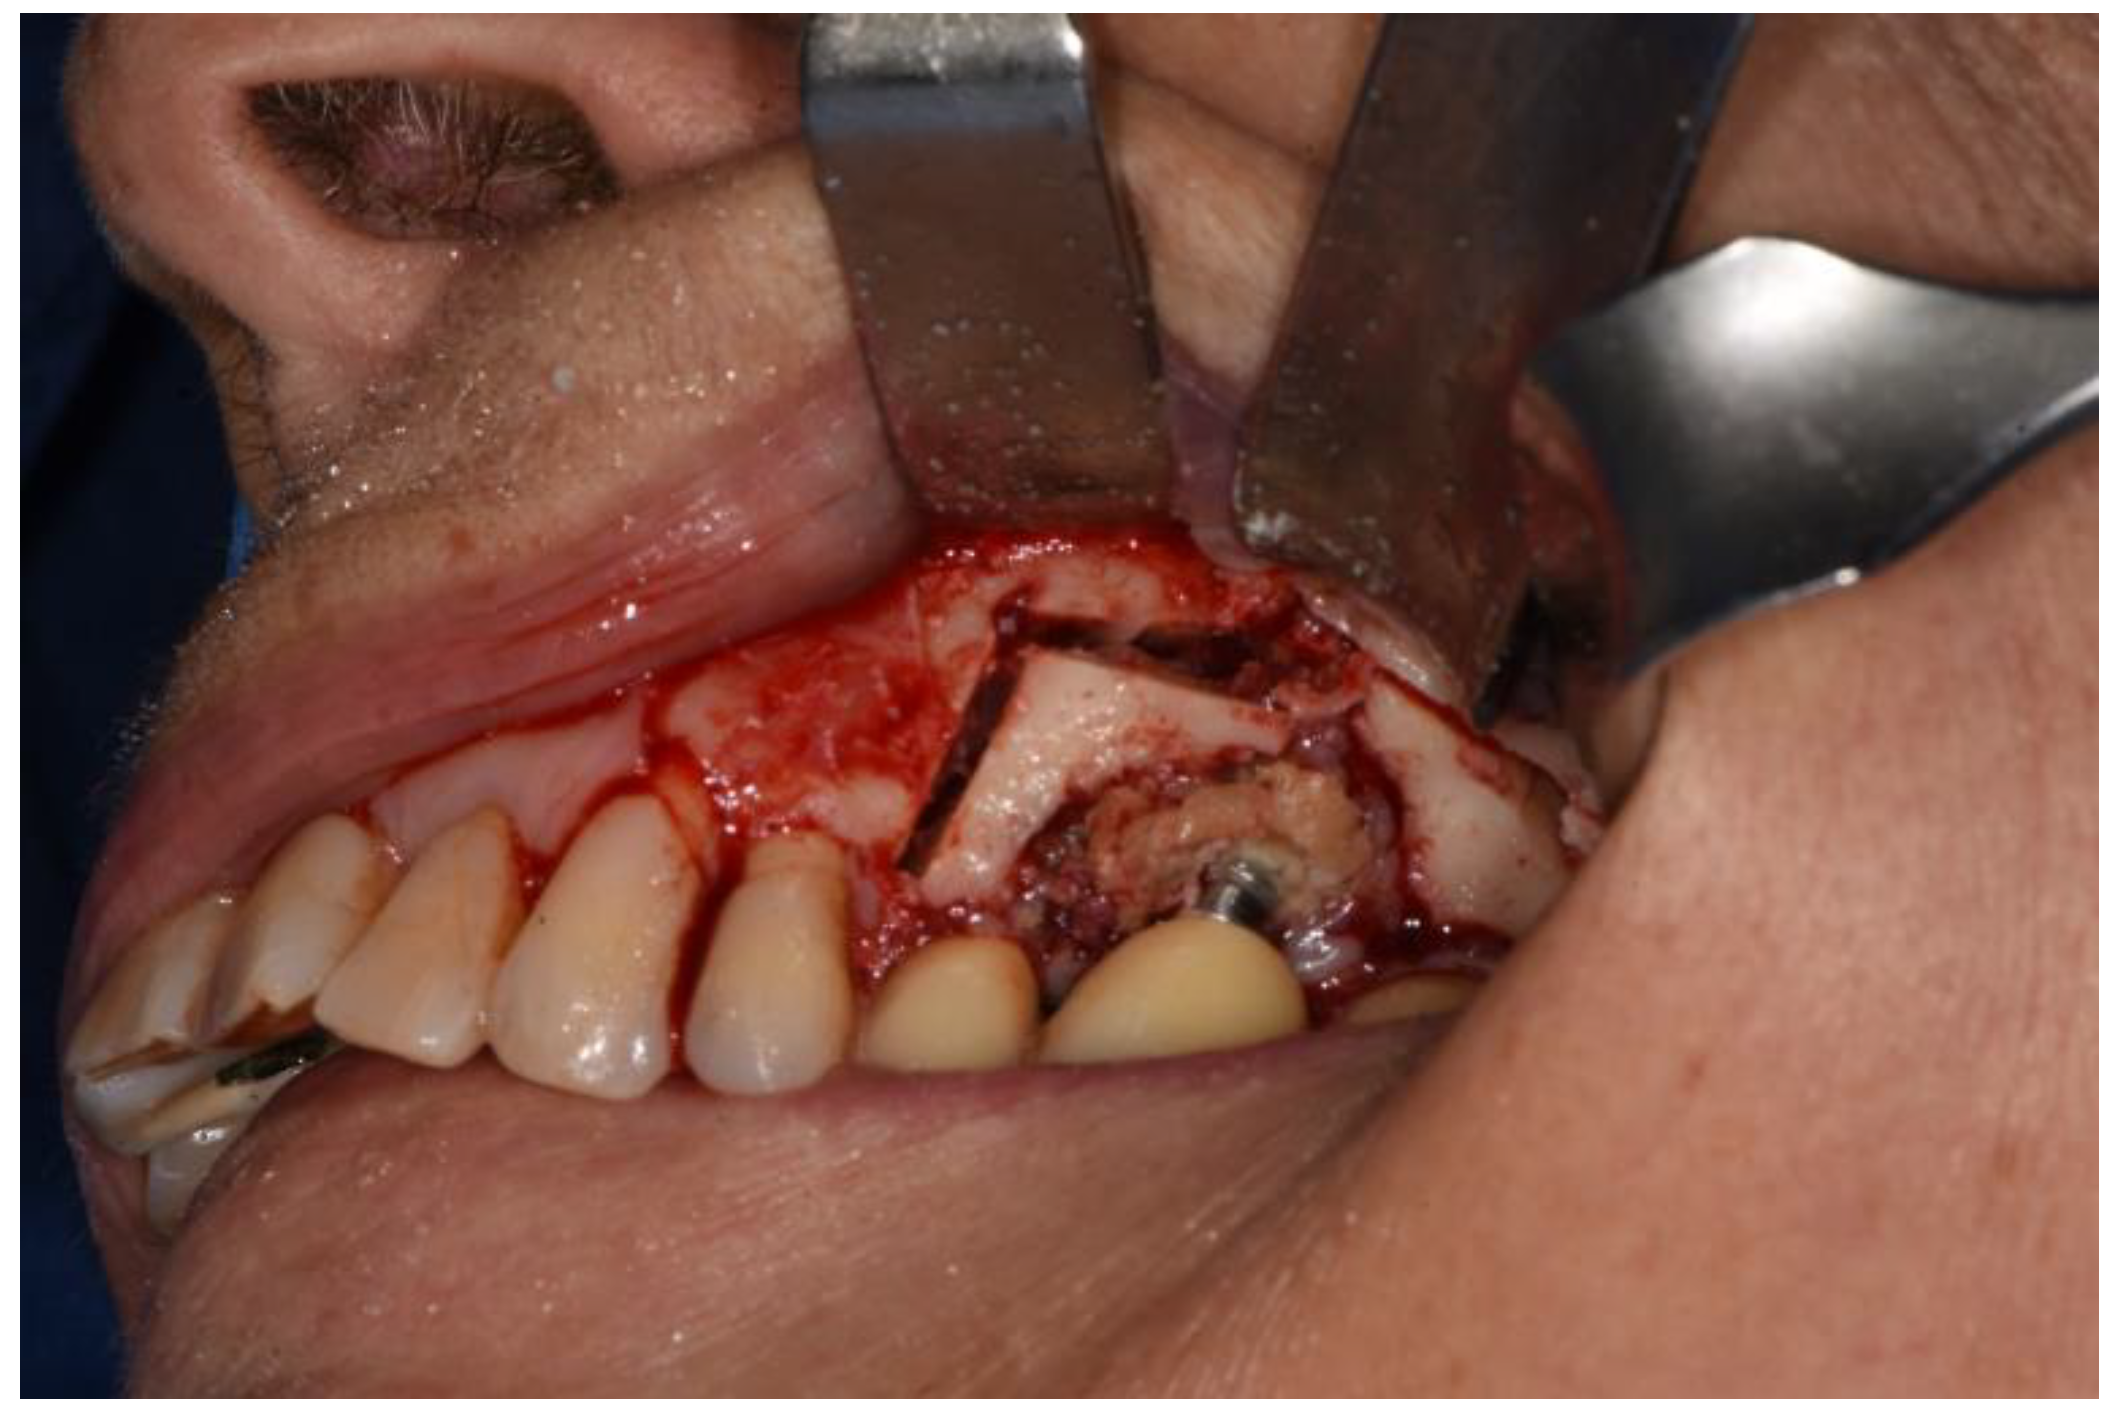

Figure 1. Preoperative CBCT showing a spontaneous bisphosphonates related osteonecrosis of the (upper) jaw in a patient with multiple myeloma treated with zoledronic acid (4 mg × 18 doses).